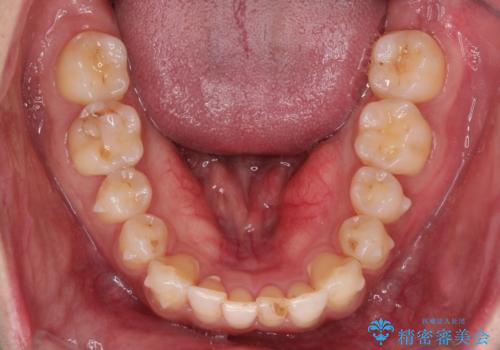

初診時の歯並びの状態としては、下顎に中等度のがたつき(叢生)がある状態でした。

抜歯は行わず下顎の奥のスペースを利用して歯をスライドする方法の他に親知らずの抜歯そして上下ともに歯列弓の拡大やディスキング(歯と歯の間の隙間を作る処置)を行い叢生を改善しました。

歯の大きさの不揃いが原因の正中のズレは、ディスキング量を調整することで合わせました。